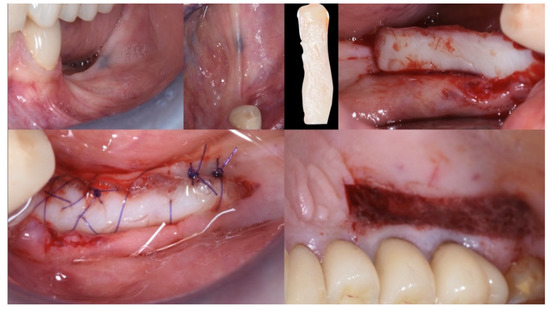

Figure 6.

Guided Bone Regeneration. Flex Cortical Sheet (FCS) was positioned to cover the bone grafts.

The FCS sheet (Osteoxenon®, Flex Cortical Sheet, Bioteck SpA, Arcugnano, Italy) was shaped and trimmed to match the dimension of the regenerated area. The FCS was first tried in place and then glued in its final position to cover the grafts. The final width of the regenerated surgical site was 10 mm (Figure 5).

The mesial and distal papillae of the last tooth in the augmentation area were closed with a double sling 4.0 polyglactin suture (Flysorb®, Butterfly, Agrate Brianza, Italy) [29,31]. One or two horizontal mattresses were placed in the middle of the ridge to put pressure sideways on the new ridge and coronally advance soft tissue. The last is usually a continuous locking mattress, but even a single interrupted suture could work fine.

The final assessment showed both vertical and horizontal gains immediately after the surgical procedure (Figure 7). The profile of the atrophic ridge has turned from concave to convex.

Figure 7.

Comparison between the edentulous ridge before the surgery and immediately after the bone augmentation procedure.